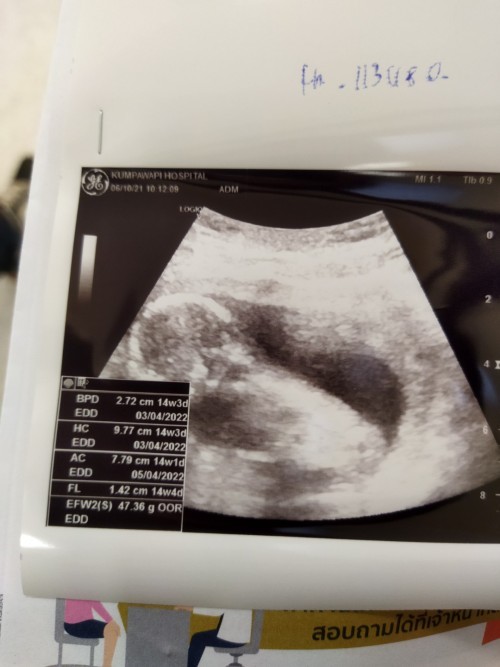

ซาวตอน14wค่ะ ตอนนี้19wแล้ว ทีมมีนาค่ะ🥰

14w 3d นัดผ่าคลอด 21 มีนา 65 ยังไม่รู้เพศเลย ... 😘